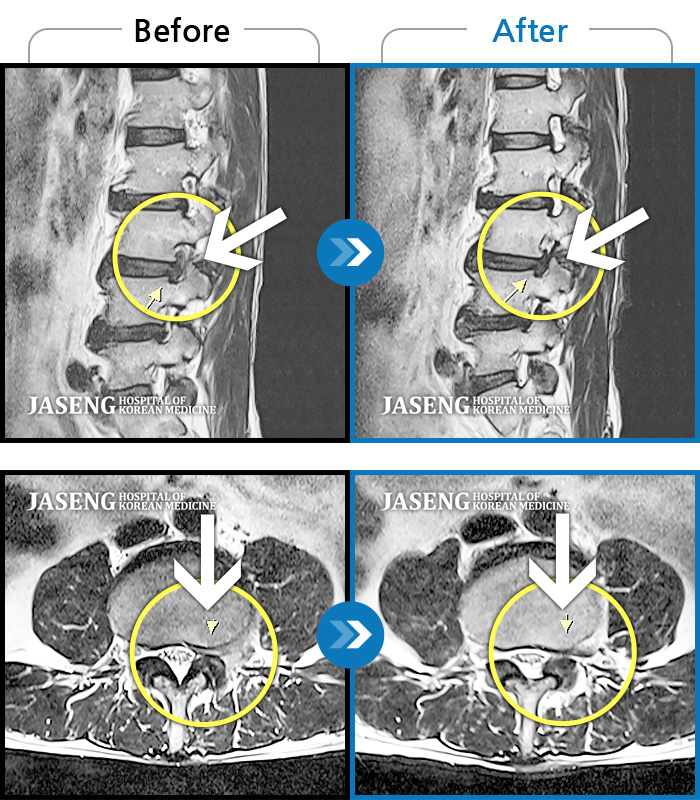

허리디스크

광주 · 김준수 원장

하부 요추, 골반 양측 통증, 좌측 다리 당김 및 통증

촬영시기

2017.10.06 ~ 2018.06.16

2018.06.22

조회수 10,212